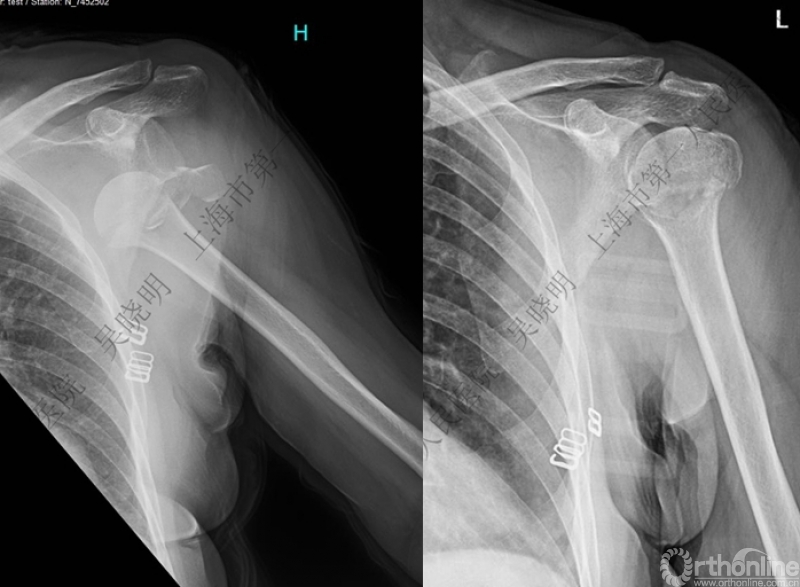

下图考虑为孤立性的大结节骨折?

看完片子,你会发现高质量的平片甚至3D CT也难以发现

X线看不清骨折线,三维CT也看不清